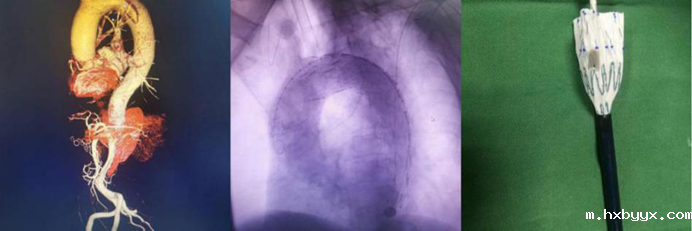

血管疾病专业组:常规开展主动脉夹层的腔内手术、胸主动脉瘤、腹主动脉瘤的腔内手术和开放手术、颈动脉内膜剥脱和支架置入手术、肝硬化、门静脉高压症断流、脾肾静脉及门腔静脉分流、下肢动脉闭塞症、深静脉血栓形成、糖尿病足、血栓闭塞性脉管炎、动脉栓塞等疾病的外科血管旁路搭桥,血管成型,静脉动脉化,球囊导管取栓,腔静脉滤器植入,肠系膜静脉血栓形成经股动脉穿刺肠系膜上动脉持续溶栓治疗,大、小隐静脉曲张微创手术,下腔静脉、股动脉等血管损伤的救治。并成功开展目前最前沿的高难度主动脉弓三开窗腹膜分支支架置入术。

腹主动脉腔内隔绝术

胸主动脉开窗、覆膜支架置入术